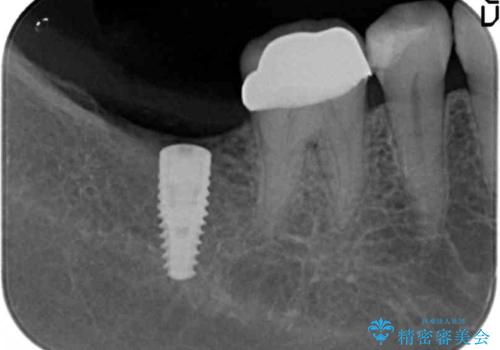

骨との結合する期間が早く、大きな咬合力にもしっかりと耐えることのできるストローマンインプラントを用いた咬合機能回復を計画します。

- 44万円(ストローマンインプラント・チタンカスタムアバットメント・仮歯・フルジルコニアクラウン)費用は治療当時の料金となります